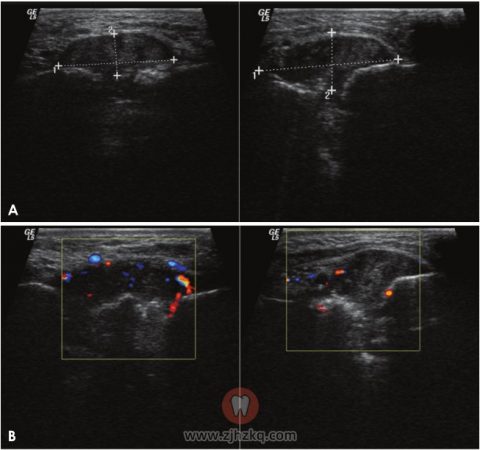

图6.全景片显示,种植体周围有边界不清的骨质破坏。根尖片显示增大的软组织影。

图7.A.B超显示边界清楚的不均匀肿块(30 mm×15 mm),可见局限性骨质破坏。B.彩色多普勒超声图显示新形成的血管供应肿块的内部及周边。